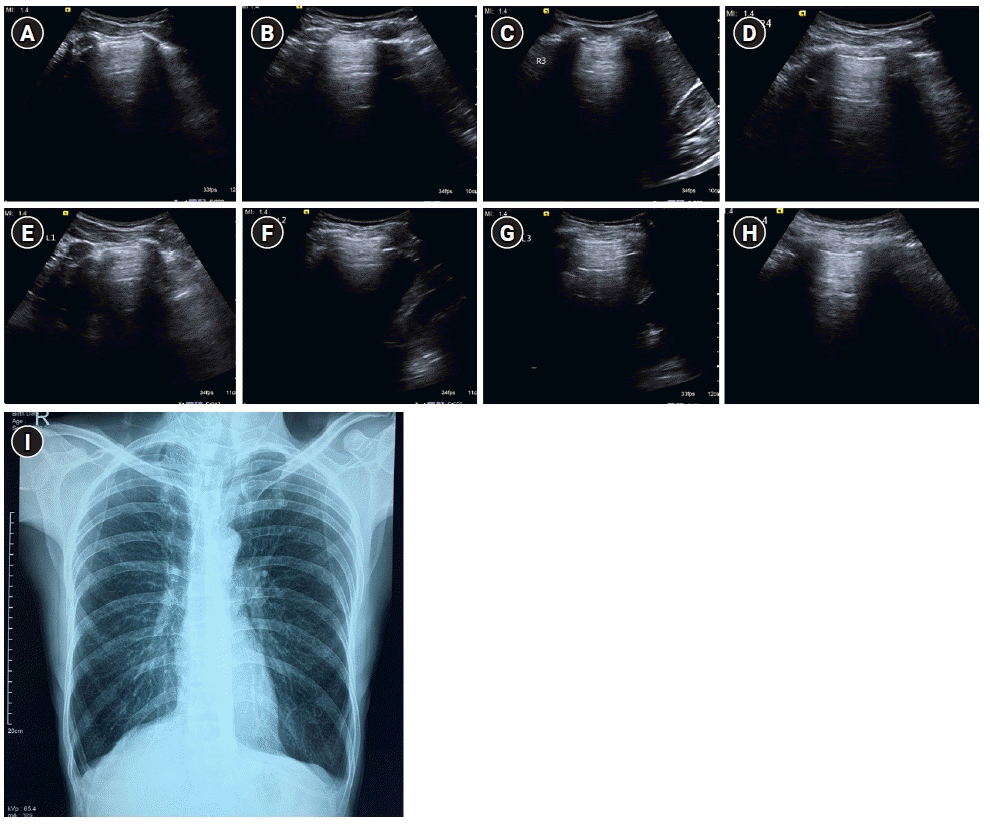

Figure 7.

A profile. Sagittal greyscale ultrasound scans (A-H) of eight lung zones in bilateral anterolateral chest wall revealing the A-profile A-lines with lung sliding and absence of B-lines in a 30-year-old afebrile male with a history of chronic cigarette smoking, presenting with dyspnea, diagnosed as exacerbation of chronic obstructive pulmonary disease/asthma on ultrasound. (I) Findings on chest X-ray were seen to be concordant. Bilateral lung fields appear hyperinflated with rounded costophrenic angles and flattening of hemidiaphragm.